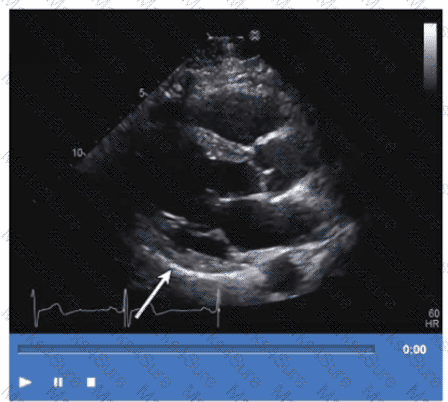

Which coronary artery territory is associated with the wall motion abnormality demonstrated in this video?